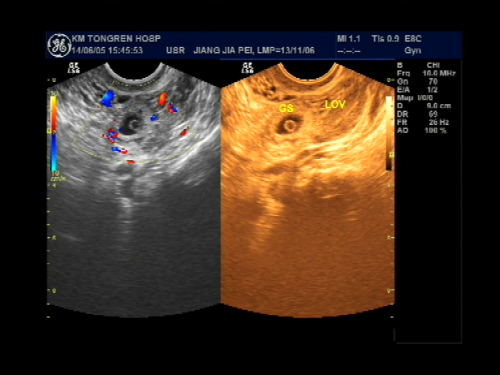

受精卵在子宫体腔以外的地方着床成为异位妊娠,习称宫外孕,是妇产科常见的急腹症,发病率约1%,是孕产妇的主要死亡原因之一。根据受精卵在子宫体外种植部位不同可分为:输卵管妊娠、卵巢妊娠、腹腔妊娠、阔韧带妊娠、宫颈妊娠,其中以输卵管妊娠最常见,占95%左右,而壶腹部妊娠占75%。一般来讲,输卵管有异常的育龄妇女如输卵管炎症、输卵管手术史、输卵管发育不良或功能异常者易导致异位妊娠,其他例如辅助生殖技术、避孕失败、子宫肌瘤或者子宫内膜异位症也容易导致疑问妊娠的发生。根据输卵管妊娠的病理特点可分为以下4型:流产型、破裂型、陈旧性、继发性,主要临床表现是停经后腹痛与阴道出血,当腹腔内出血量大或者疼痛剧烈时可出现晕厥与休克,超声检查下可观察到:宫腔内空虚,宫旁出现似孕囊样包块或者不均质包块,盆腔积液等等,再结合病史、血HCG、尿HCG结果分析,一般可诊断早期异位妊娠。